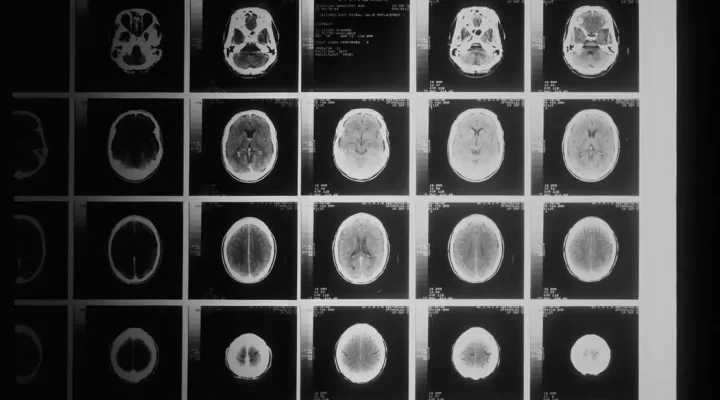

Devamı Share on: MakalelerKişiye Özel Dinamik Kanser Tedavisi 2025 4 ay önce eklendi Editör Adaptif Radyoterapi İle Kişiye Özel Ve Dinamik Kanser Tedavisi Devamı →